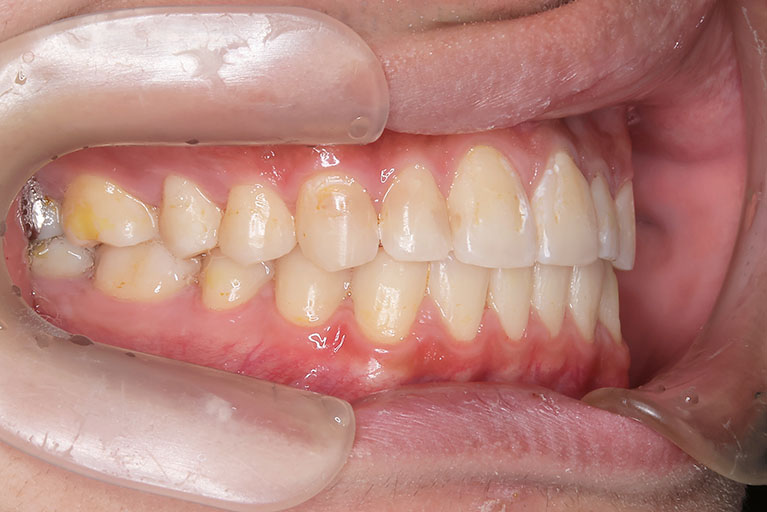

受け口を気にされ、他院からの紹介で来院された患者さんです。

小学2年生、生え変わりの時期から小児矯正を開始しました。

小児矯正で前歯の咬み合わせを改善し、

永久歯列完成後の中学生から非抜歯治療にて本格矯正を開始。

配列し仕上げました。